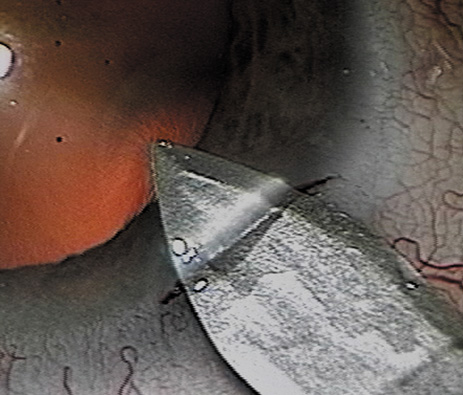

HYDRODISSECTION Hydrodissection can be performed after the surgeon has successfully completed capsulorrhexis.97 If the capsulorrhexis is not intact, fluid forced around the interior of the capsule may cause the bag to splay open. With capsulorrhexis, hydrodissection is a safe and extremely useful maneuver. Hydrodissection can be thought of as two maneuvers: hydrodelineation and cortical cleaving hydrodissection. By placing a 27-gauge cannula on a syringe filled with balanced saline solution (BSS), the surgeon can direct fluid beneath the residual anterior capsular rim to create a cleavage plane. Depending on the direction the fluid wave takes, different lamellae of the cataract will be separated. Hydrodelineation is the term used when the cleavage plane separates the adult nucleus from the fetal nucleus or the adult nucleus from the more peripheral epinucleus. Hydrodelineation often results in the characteristic golden ring sign (Fig. 11). Cortical cleavage occurs when the cortex is separated from the capsular bag (Fig. 12). Finding the cortical cleavage plane may be facilitated by gently lifting the capsular margin away from the cortex with the BSS cannula before injecting. Several small bursts of fluid allow the surgeon to monitor progress of the fluid wave. When dealing with a soft nucleus, the authors strive to perform true cortical cleaving hydrodissection. For a hard nucleus, hydrodelineation allows manipulation of less of the nuclear bulk, although the remaining epinuclear shell must be addressed in an additional step. Hydrodelineation is particularly useful if the nucleus is not freely mobile after cortical cleaving hydrodissection.